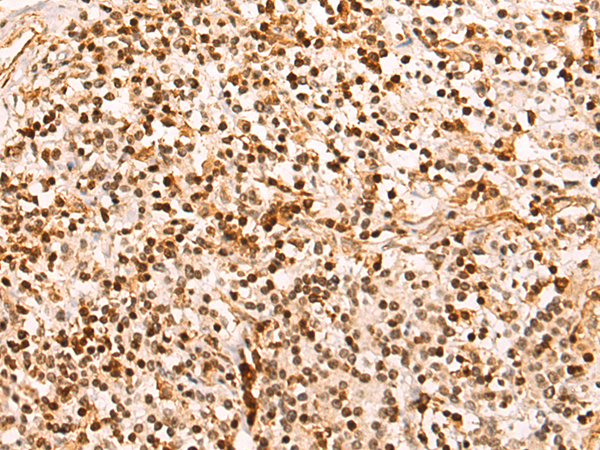

分类: 科研抗体货号: P12486别名: CDX3; CDX-3; CDX2/AS应用: WB,IHC反应种属: Human, Mouse